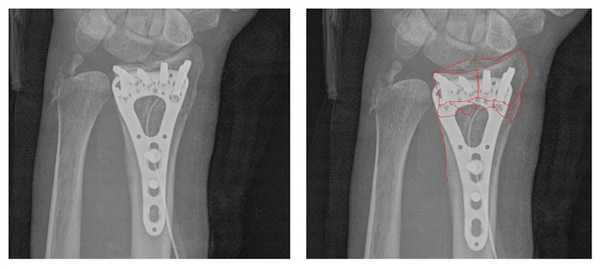

Произведён доступ к месту перелома по ладонной поверхности предплечья. При ревизии выявлено множество мелких осколков в метафизарной области по волярному кортексу. Произведена открытая репозиция перелома, временная фиксация спицами. Накостно уложена пластина VA-LCP™ Two-Column Distal Radius Plate

После рентгенконтроля производится введение блокируемых винтов диаметром 2,4 или 2,7 мм.

Данная пластина отлично подходит для фиксации оскольчатых переломов дистального метаэпифиза лучевой кости, однако в ряде случаев, когда перелом располагается более дистально, предпочтительнее использовать пластину другой конструкции (Volar rim).

Окончательный остеосинтез после проведения всех винтов выглядит на рентгенограмме примерно так. На левой части рисунка схематично отображено расположение фрагментов кости, фиксированных пластиной.